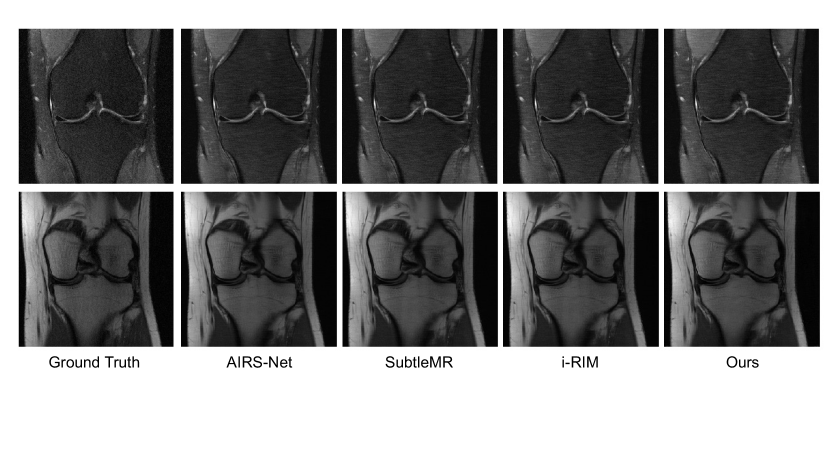

We also compare the joint networks with top single coil methods on the FastMRI benchmark. For these experiments, we use a larger version of the Interleaved network comprised of 6 joint layers with two frequency space and two image space convolutions per layer, yielding roughly 3 million parameters total.

Our results on the knee undersampled reconstruction task replicate the trends observed in the brain undersampled reconstruction task. Joint networks outperform single-domain networks, as reported in Table 2. This suggests that our joint layers can successfully process acquired, complex-valued MRI data. Further, Table 2 confirms that the success of joint learning is not specific to a certain loss landscape. Qualitative examples of reconstructions from networks trained with various loss functions are shown in Fig. 11.

The reconstructed images produced by the larger Interleaved network are qualitatively similar to those produced by the top three methods on the FastMRI leaderboard (Fig. 12). Table 3 reports reconstruction quality measures for Interleaved network and the top single-slice methods on the FastMRI benchmark. Interleaved network achieves results that are close to the state of the art architectures specifically tuned for this task. We emphasize that our goal is not to attain state of the art performance on the FastMRI benchmark, but rather to show that simple layers comprised of both frequency and image space convolutions achieve reasonable performance on this benchmark while offering flexibility for correcting a wide range of other artifacts, and for correcting multiple artifacts present simultaneously.